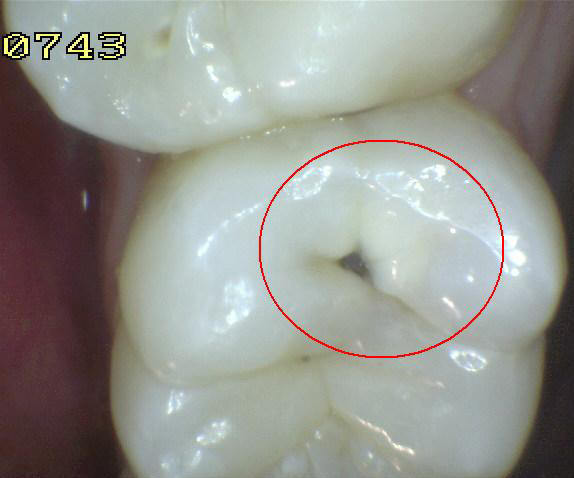

2. SOMBRA SUBYACENTE DE DENTINA (SIN PERDIDA DE INTEGRIDAD ESTRUCTURAL)

1. HALLAZGO: sombra que trasluce una restauración

1. CRITERIO DE DIAGNOSTICO: área oscurecida, sombra intrínseca, que puede aparecer gris, azúl o café

1. ICDAS 4

2. DIAGNOSTICO

1. lesión cariosa no cvitacional

2. TRATAMIENTO

1. Operatorio

2. ACTIVIDAD

1. (Activa / inactiva